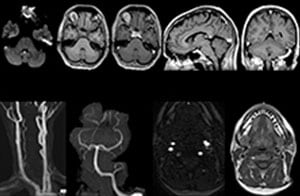

Routineuntersuchung der Halswirbelsäule

Dieser Patient wurde mit Kopfschmerzen vorstellig, die sich bei einer Flexion des Nackens verschlimmerten, und wir sehen hier eine Chiari-Malformation vom Typ I mit niedrig liegenden Kleinhirntonsillen sowie degenerativen zervikalen, thrombolytischen Veränderungen.